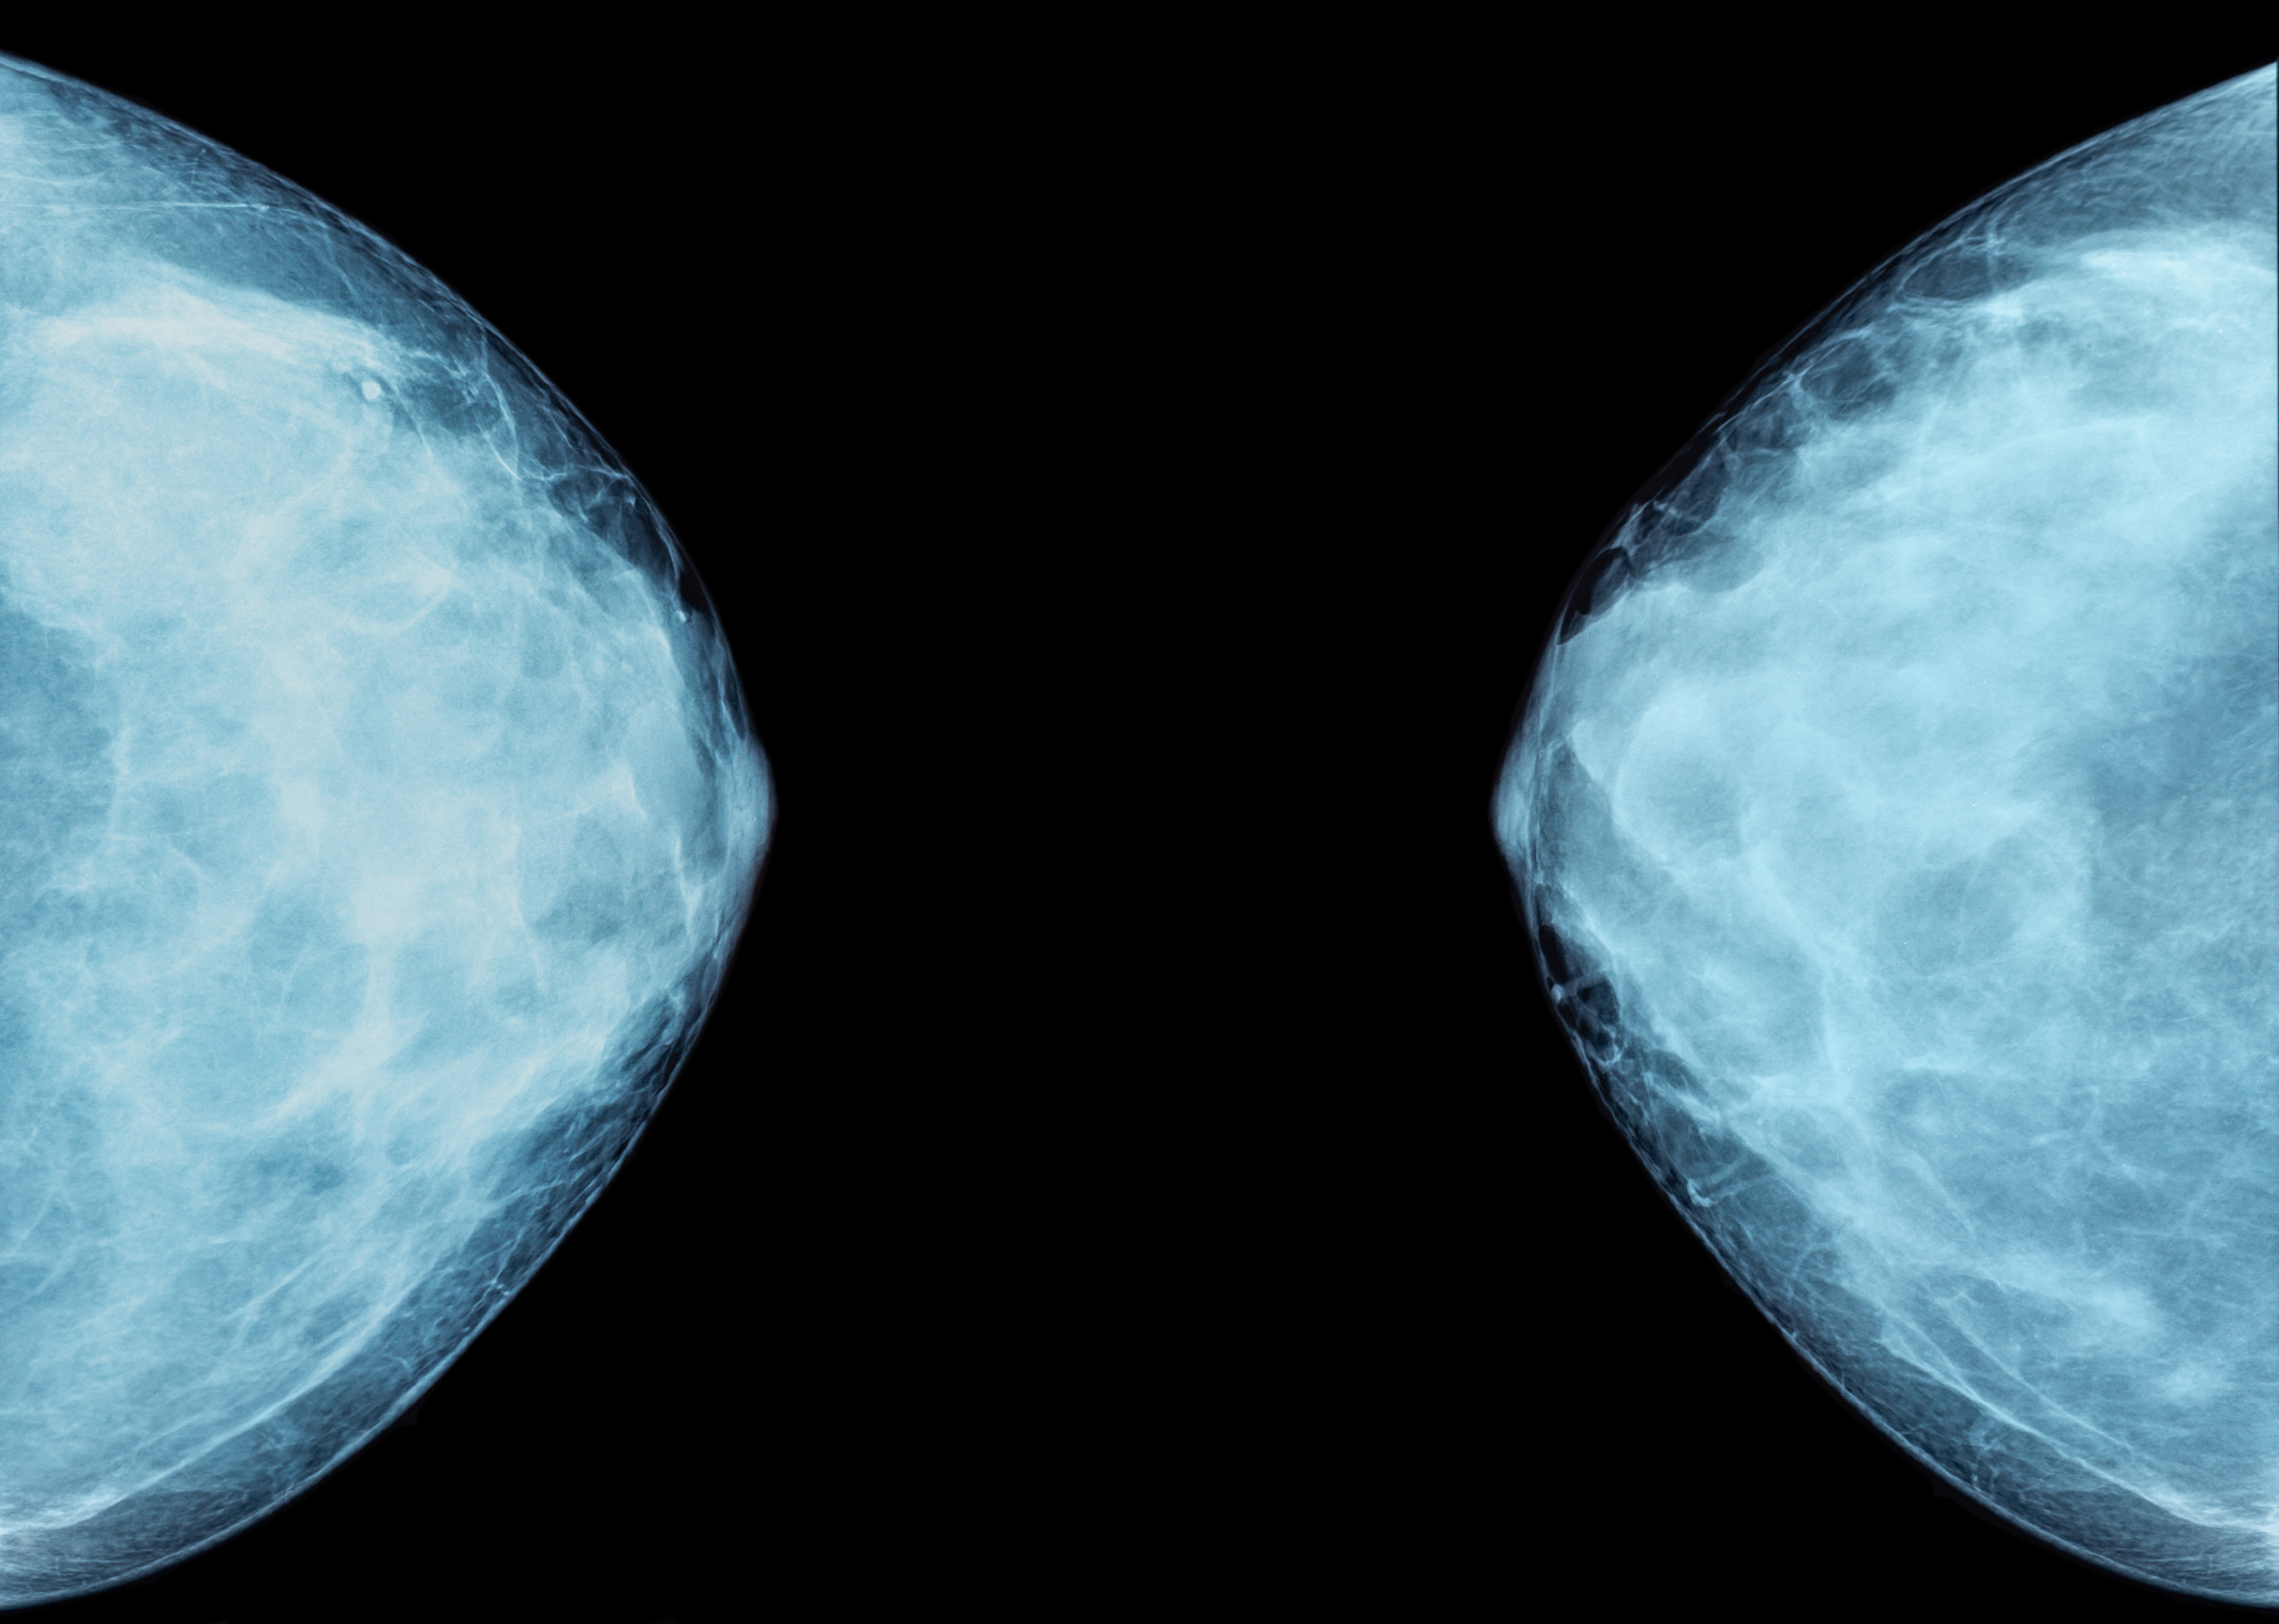

2/ Mamografické čtení snímků pomocí umělé inteligence

Ve screeningu nádorů prsu je standardem takzvané dvojí čtení mamografických snímků, jež podstatně zvyšuje spolehlivost vyhodnocení abnormálních nálezů. I do této oblasti dnes proniká umělá inteligence (AI) – v podobě takzvaného třetího, dodatečného čtení. To zvyšuje senzitivitu vyšetření až o 20 % a přináší hodnotícím radiologům větší jistotu. Podrobnosti ZDE.

Zdroj: medicina.cz